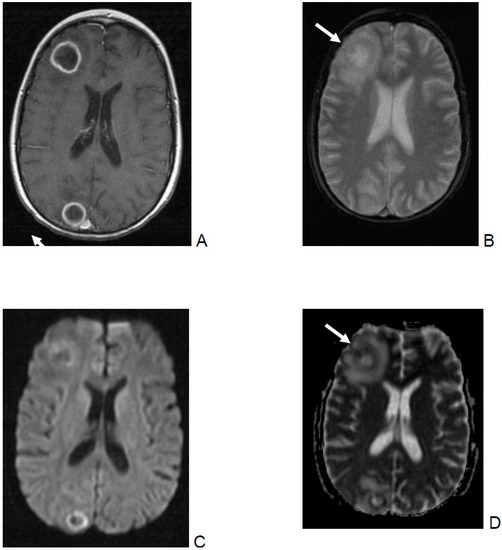

- DWI and ADC were evaluated for infarction, lesions with central restricted diffusion, lesions with a rim of restricted diffusion, and others. Infarction was defined as territorial, cortical, and sub-cortical lesions without nodular or ring-like aspect. Non-infarction-DWI restrictions, with nodular or ring-like aspect, were classified as lesions with central or rim-like restricted diffusion. Others included patients with cerebritis and bleeding.

| Outcome | Infarction | Central Restricted Diffusion | Rim Restricted Diffusion | Others |

|---|---|---|---|---|

| Total number of patients | 7 | 10 | 3 | 2 |

| Died | 3 | 4 | 1 | |

| Severe neurological sequelae | 3 | 3 | 0 | 1 (cerebritis) |

| Favorable outcome | 1 (focal pericallosal vasculitis) | 3 | 2 | 1 (bleeding) |